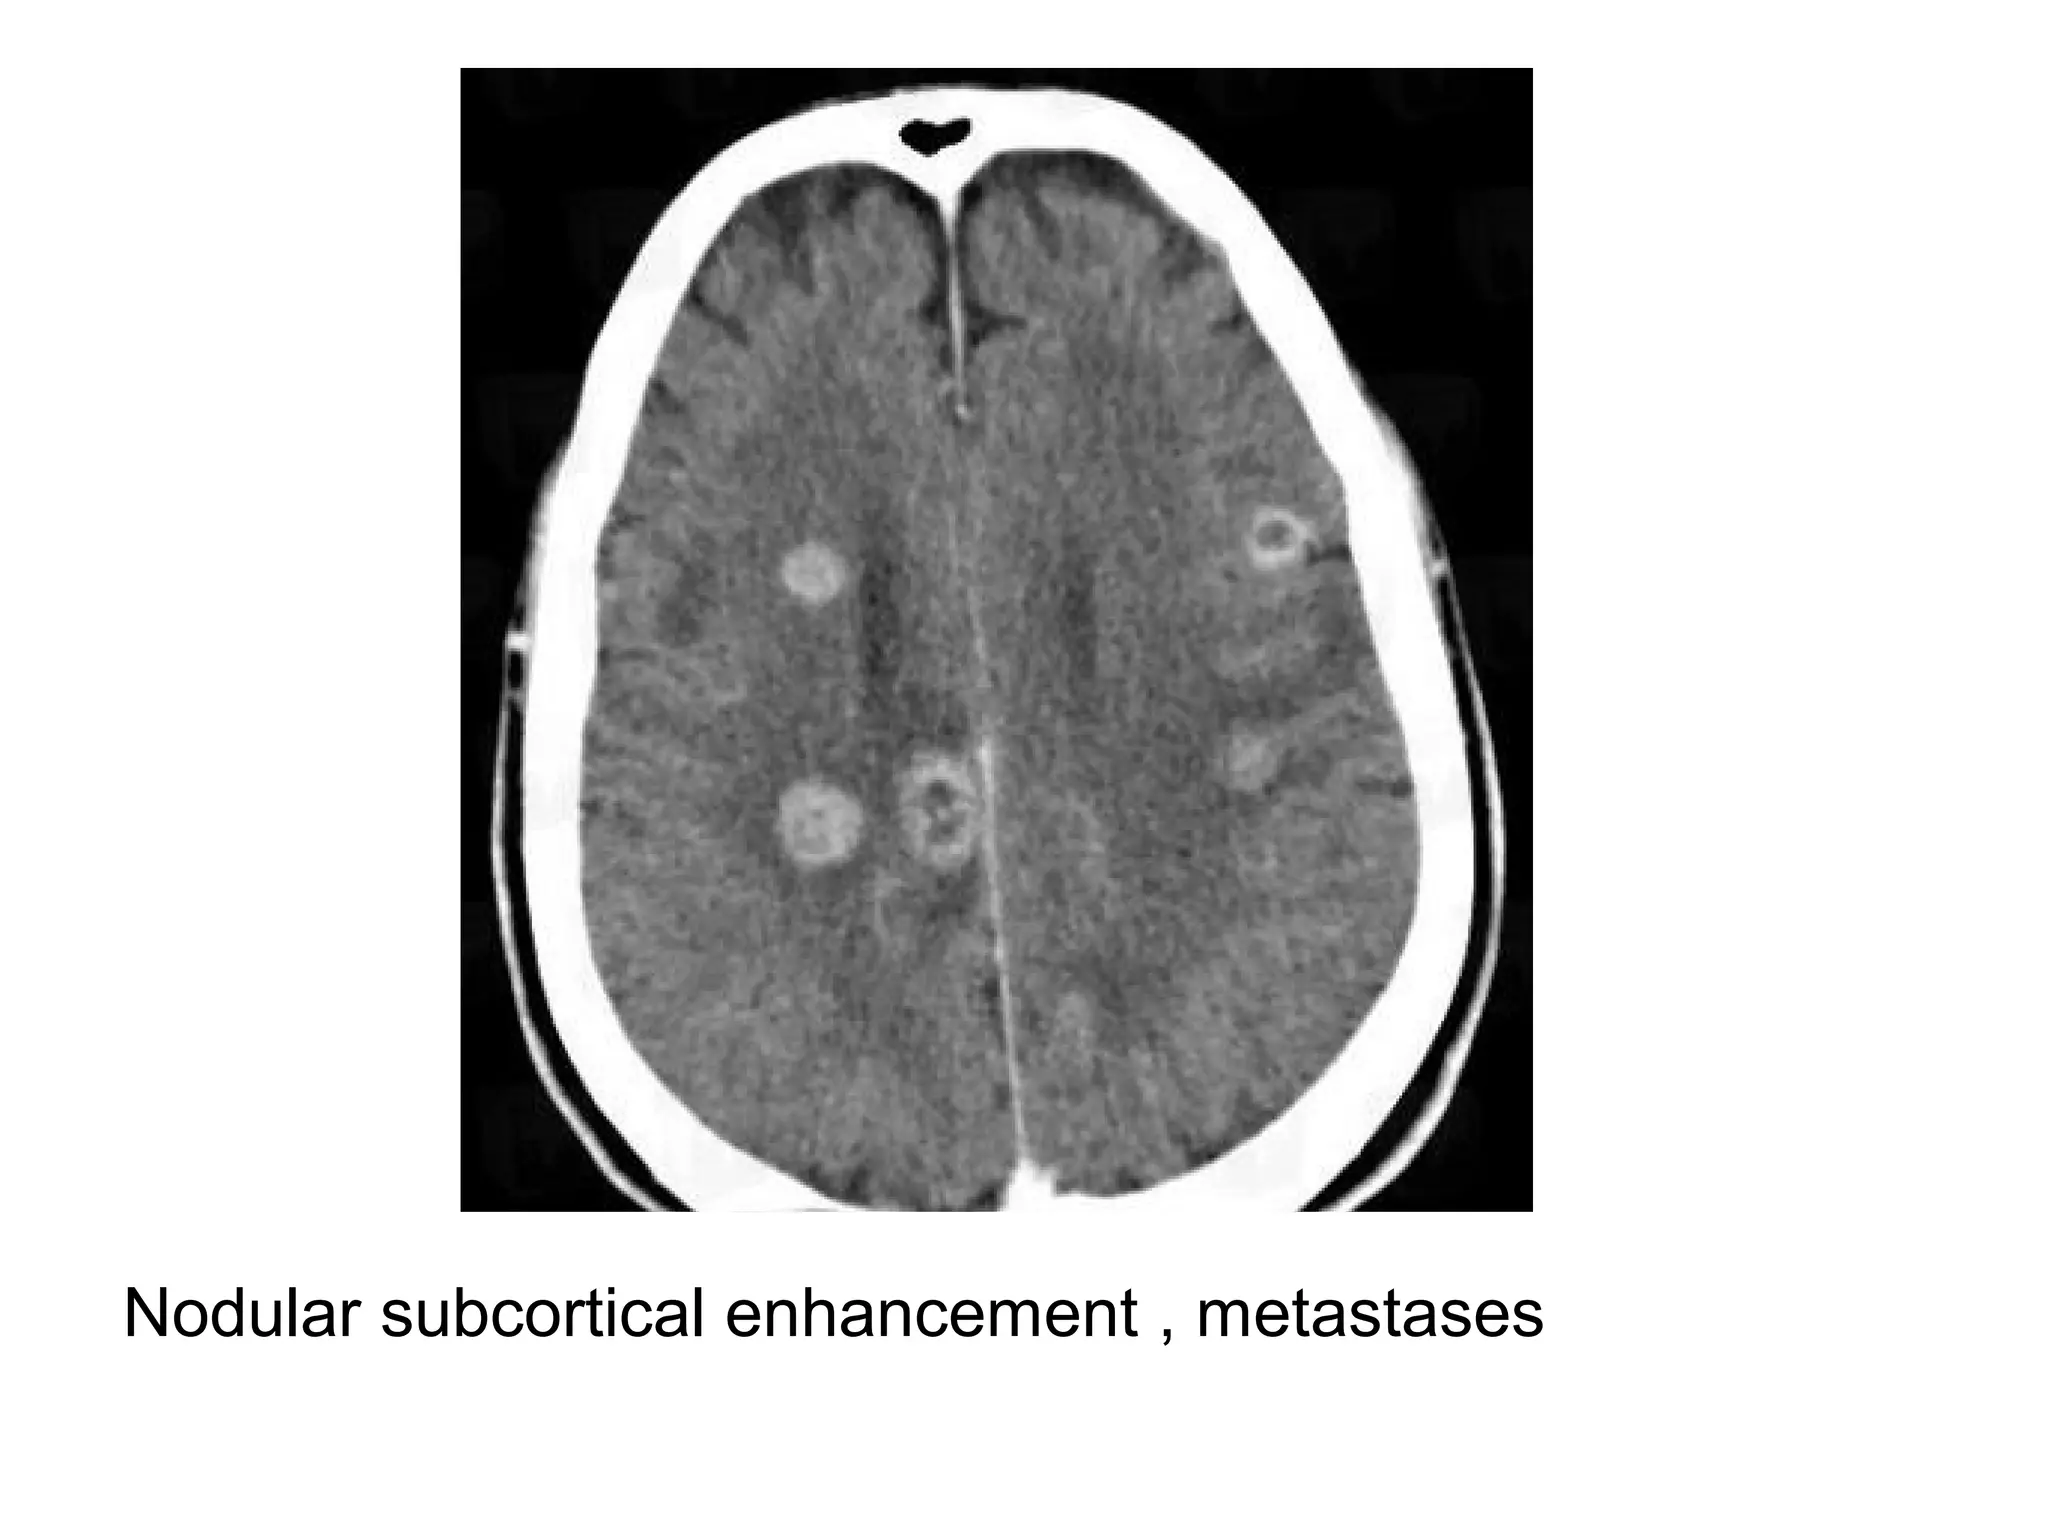

Subcortical nodular enhancement , Diagram illustrates nodular lesions near the

gray matter-white matter junction and one near the deep gray matter , this

pattern is typical for metastatic cancer and clot emboli , because of their

typical subcortical location , metastases often manifest with cortical

symptoms or seizures while the lesions are small (often <1 cm in diameter)

Nodular subcortical enhancement , metastases